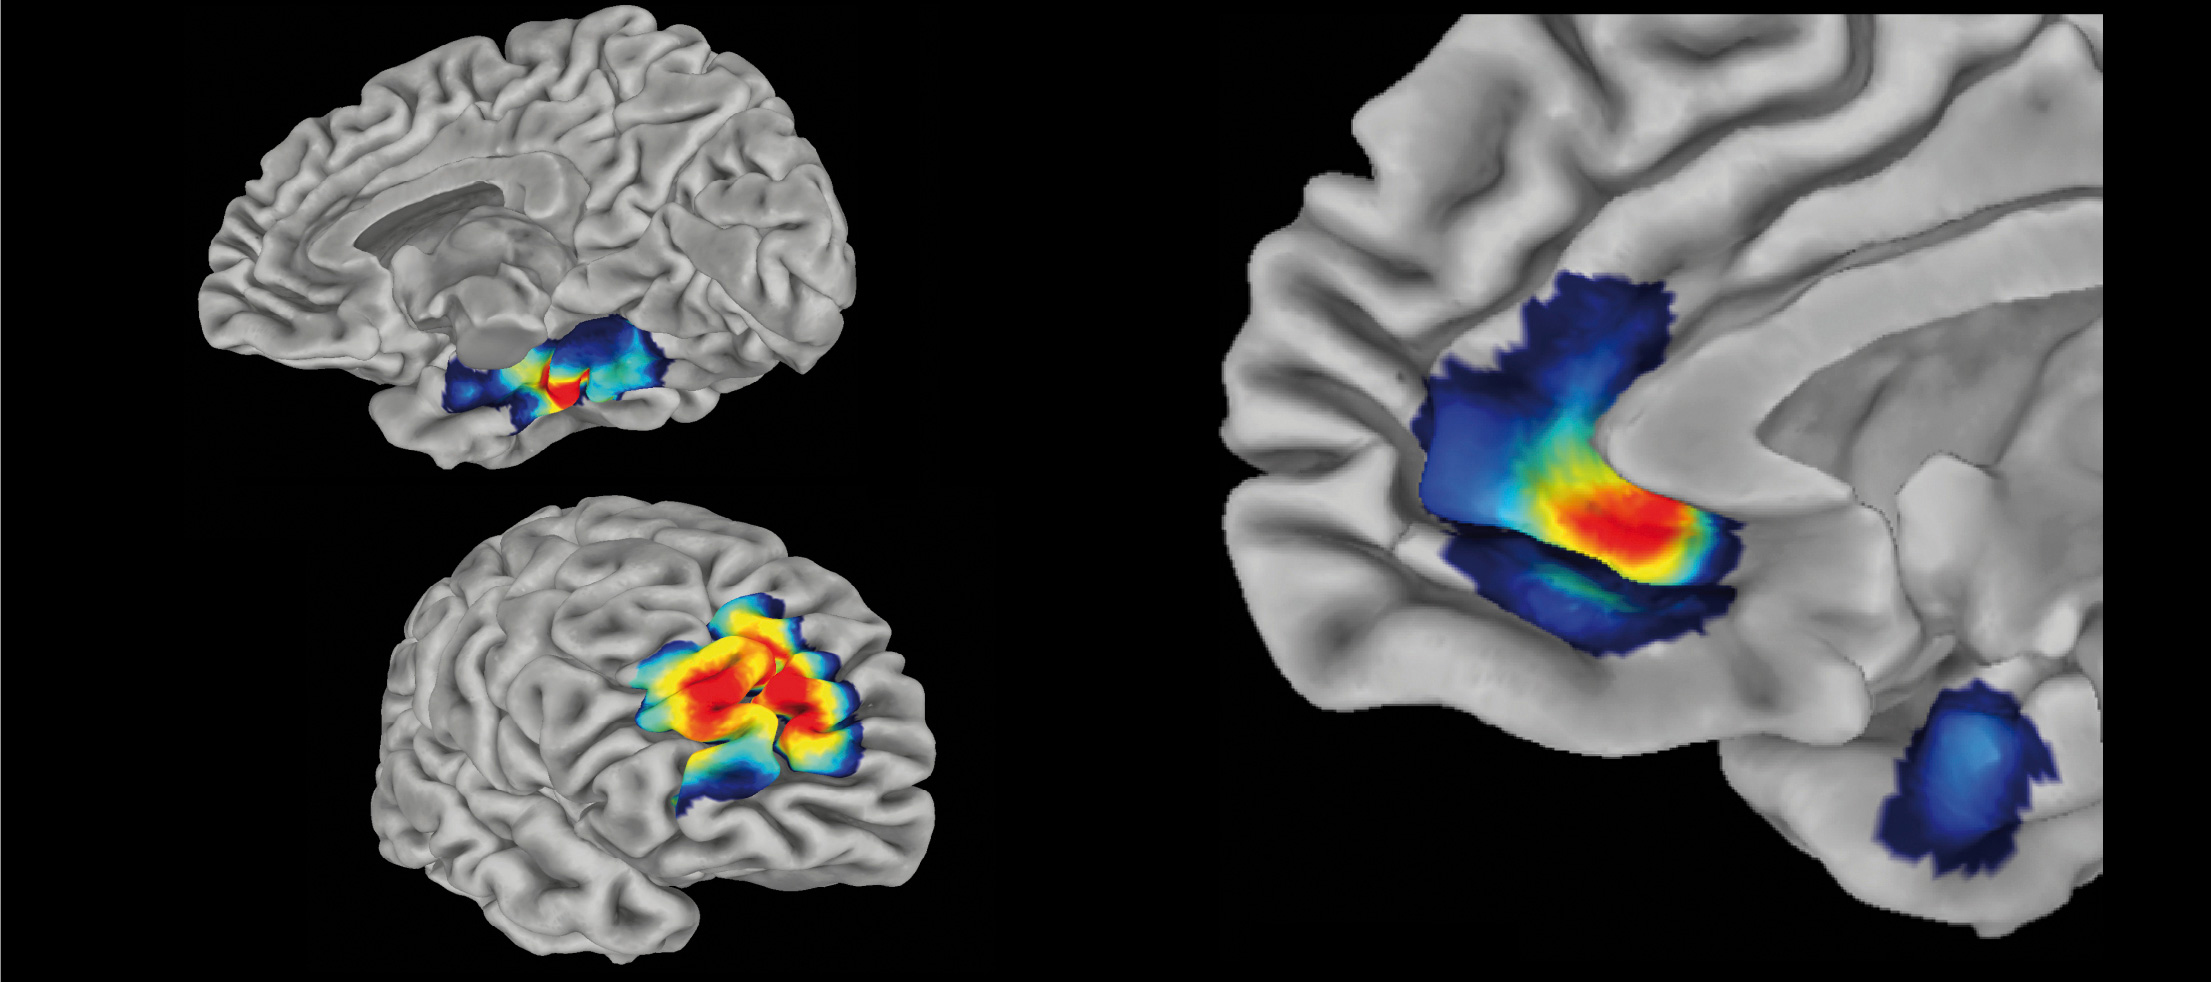

- Prediction of Antidepressant Response Using fMRI